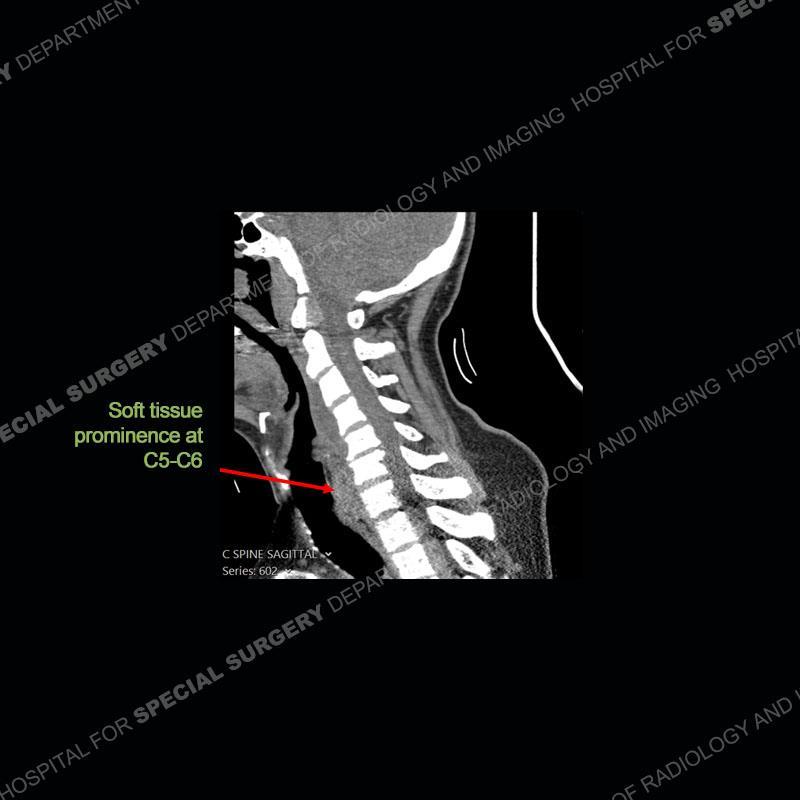

The radiographs demonstrate a prevertebral soft tissue fullness centered at C5-C6 that persists even on extension. There is a slight loss of disc height at C5-C6. The CT more readily shows the prevertebral soft tissue swelling at C5C6 where there is a punctate focus of gas. On the MRI, there is a marked amount of edema and a heterogeneous collection in the prevertebral soft tissue at C5-C6. Edema is present of the C5 and C6 vertebral bodies with a loss of the normal architecture about the disc space. A heterogeneous epidural collection has formed that causes compression of the spinal cord asymmetric to the left side and also precipitates severe left sided neural foraminal stenosis.

Diagnosis: Spontaneous Retropharyngeal Abscess (RPA) with Discitis/Osteomyelitis, Epidural Abscess, and Cord Compression

Spontaneous RPA in the non-immunocompromised, adult population is an extremely rare occurrence. RPA most frequently occurs in young children and most typically after a URI. It may be associated with torticollis in Grisel syndrome. In the adult population, the pathomechanism is not well understood with some suggesting a hematogenous spread or perhaps a seeding from the adjacent aerodigestive tract. The abscess as in this case can extend to involve the vertebral column and then the neural elements. At times, this process can be treated with antibiotic therapy alone but when there are neurologic symptoms and especially progression of neurologic symptoms, surgical intervention is warranted. In this case, given the extent of the process and the patient’s clinical situation, a corpectomy with fusion was performed in addition to antibiotics.